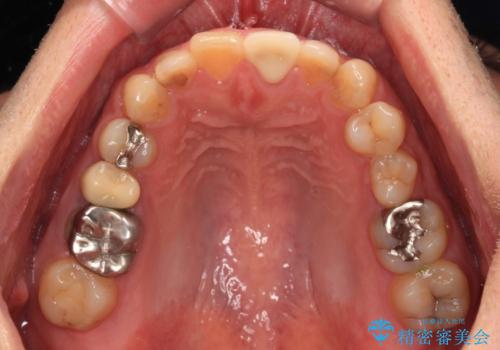

- 前歯の色を気にして来院された患者様です。

むし歯で神経が取り除かれており、歯の変色と充填材の変色などにより、つぎはぎのような前歯となっていました。

膿の出口も認められたため、まずは根管治療を実施し、オールセラミッククラウンにて補綴治療を行うこととしました。